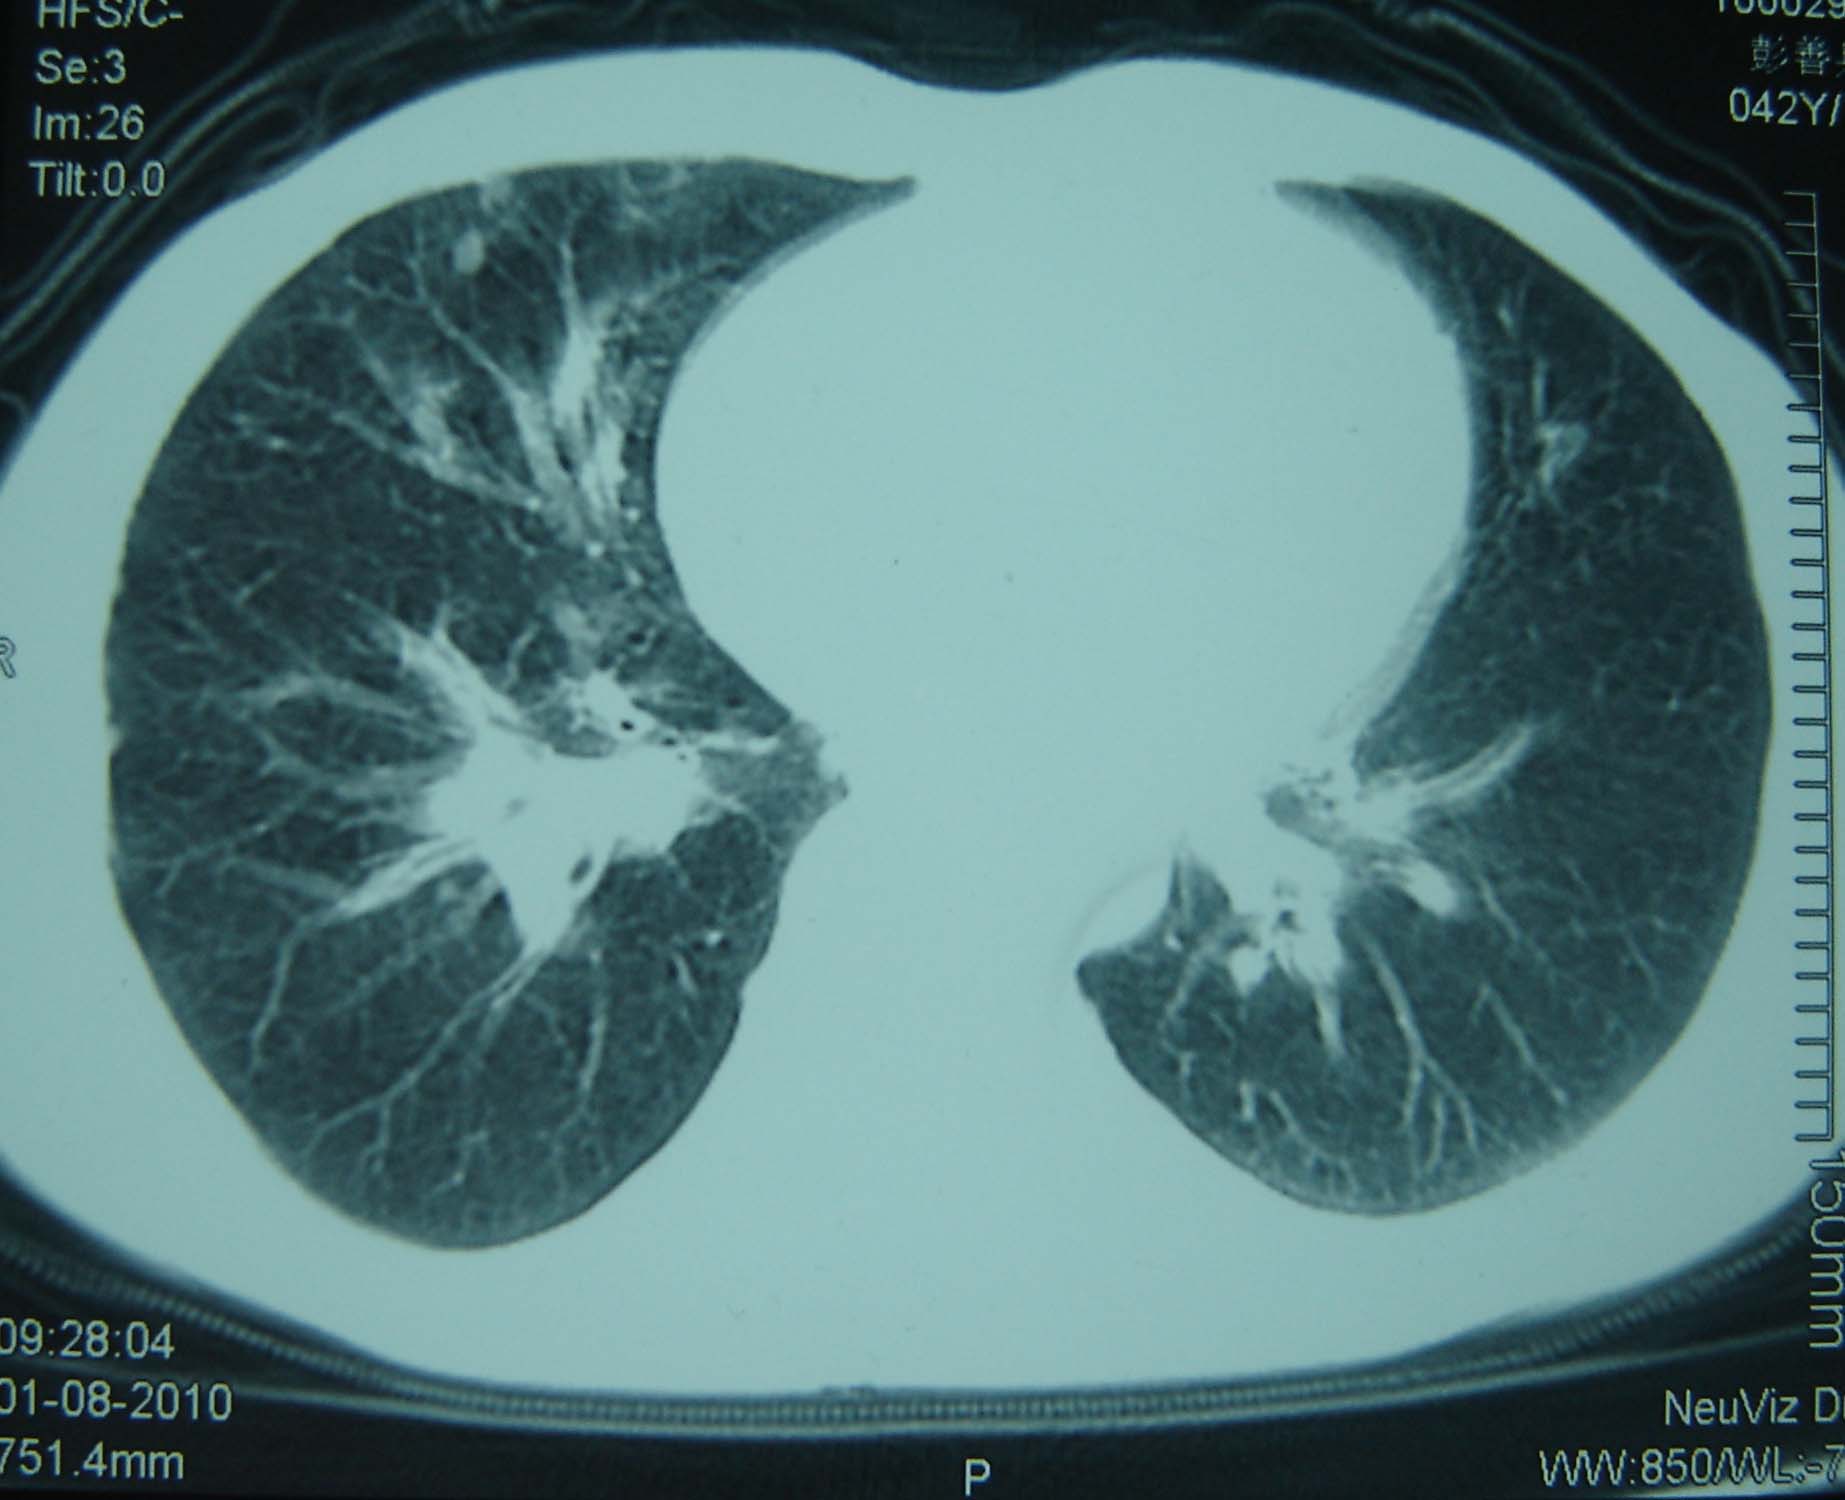

标题: CT25321:两肺多发结节 请会诊 [打印本页]

标题: CT25321:两肺多发结节 请会诊

男 、43岁,咳嗽胸痛,装修工,平时接触粉尘较多,有吸烟史10多年,纤维支气管镜检查未发现异常,胃镜、腹部b超检查亦未发现异常,颈部淋巴结活检未发现肿瘤细胞。

不能排除转移,如果不能找到原发灶,只有短期随访。

结节病?转移瘤?

结节病。

转移瘤?

1)考虑双肺及胸膜多发性转移瘤。2)肺气肿。

双肺结节病。